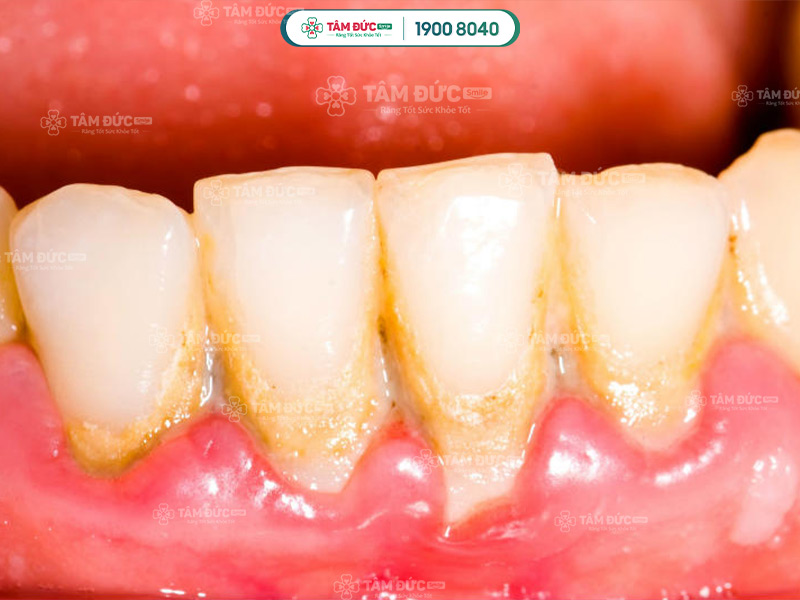

Tụt lợi có thể là biến chứng của các bệnh lý như: Viêm lợi, viêm nha chu, cao răng,... khi không được điều trị kịp thời. Các bệnh lý này chính là nguyên nhân phổ biến nhất khiến vùng lợi bị tụt khỏi chân răng.

Cao răng dày đặc là nguyên nhân làm viêm nướu và gây tụt lợi nhanh chóng